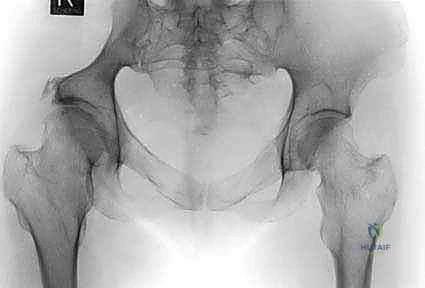

- التصوير بالأشعة السينية (X-rays): الفحص المبدئي لرصد أي تآكل أو تدمير في البنية العظمية للحوض ومفصل الورك.

- التصوير المقطعي المحوسب (CT Scan): يقدم صوراً ثلاثية الأبعاد تُظهر بدقة متناهية مدى تدمير القشرة العظمية، وهو الفحص الأهم للتخطيط الجراحي وتحديد خطر حدوث الكسور المرضية.